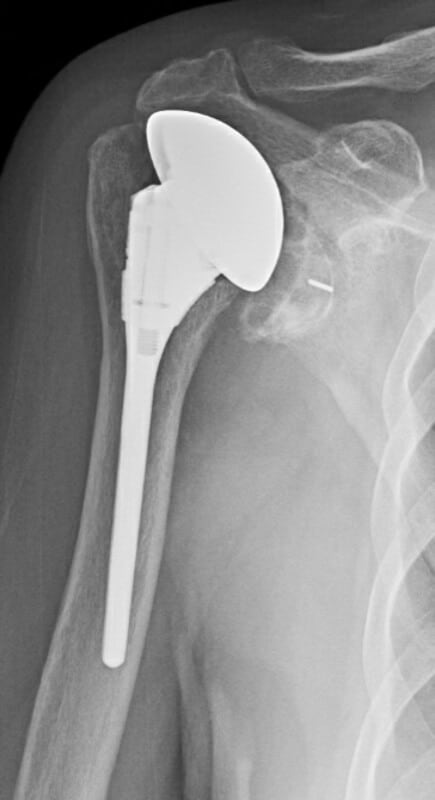

DePuy, Global Unite